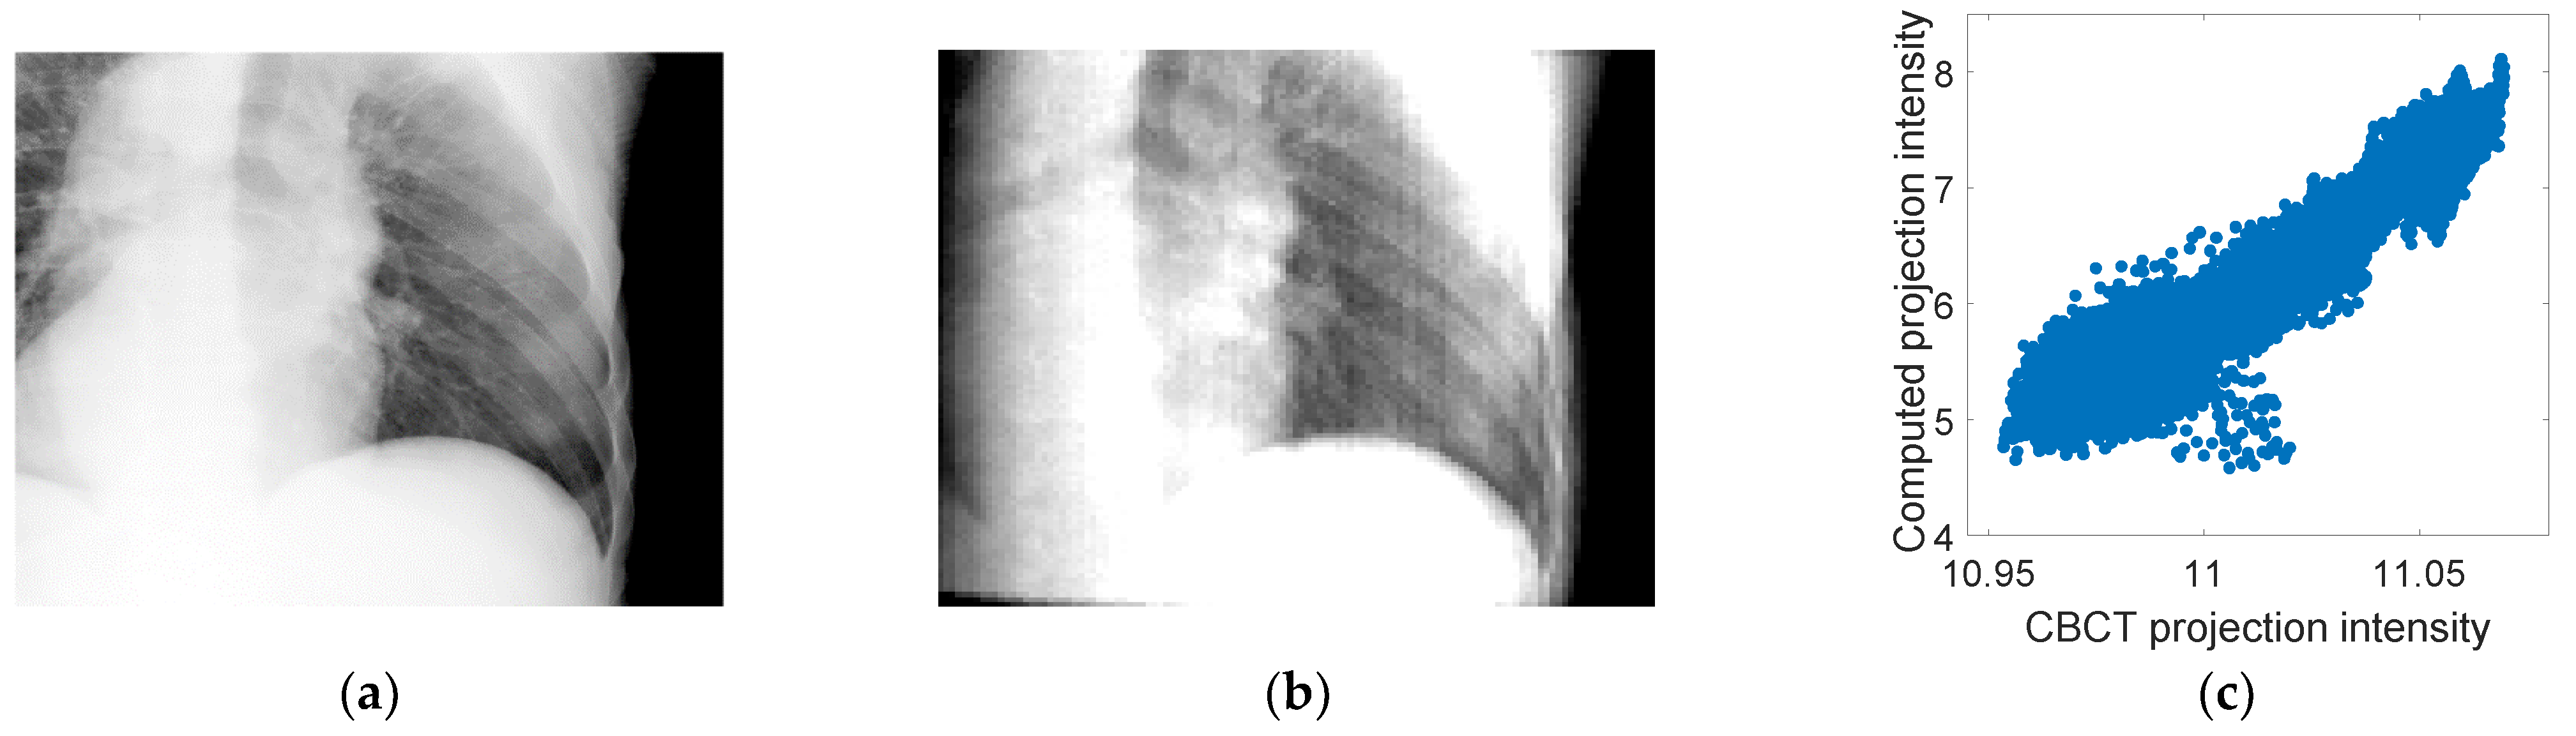

The PCA motion models derived from 4D-CBCT images were used to estimate the fluoroscopic 3D images. Firstly, a correlation analysis was conducted to measure the correlation between the intensities of a sample CBCT projection and the corresponding 2D projection computed using the estimated motion model and the 4D-CBCT reference phase. This study is important to prove the linear relationship between the intensities of the two projections as assumed in the cost function described by Equation (2). Figure 4 shows a CBCT projection and the corresponding 2D projection computed using the estimated motion model and the 4D-CBCT reference phase. A scatter plot showing the linear correlation between the intensities of the two images is shown. As can be seen from the figure, a linear correlation was found with a correlation coefficient of 96%.

Figure 4.

(a) Sample CBCT projection from patient #2, (b) the corresponding computed projection using the motion model and the 4D-CBCT reference phase, and (c) a scatter plot showing the correlation between the intensities of the two images in (a,b). A linear correlation was found between the two image intensities with a correlation coefficient of 96%.